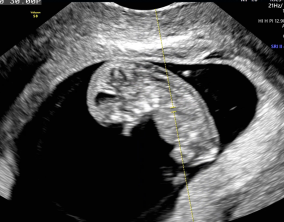

이유정 원장님은 매 순간 환자의 마음을 읽어주시는 분이었어요. 부담 없이, 그러나 가장 효과적인 방향으로 치료를 이끌어주셨고, 그 덕분에 PGT-A에서 무려 5개의 통과 배아를 얻…